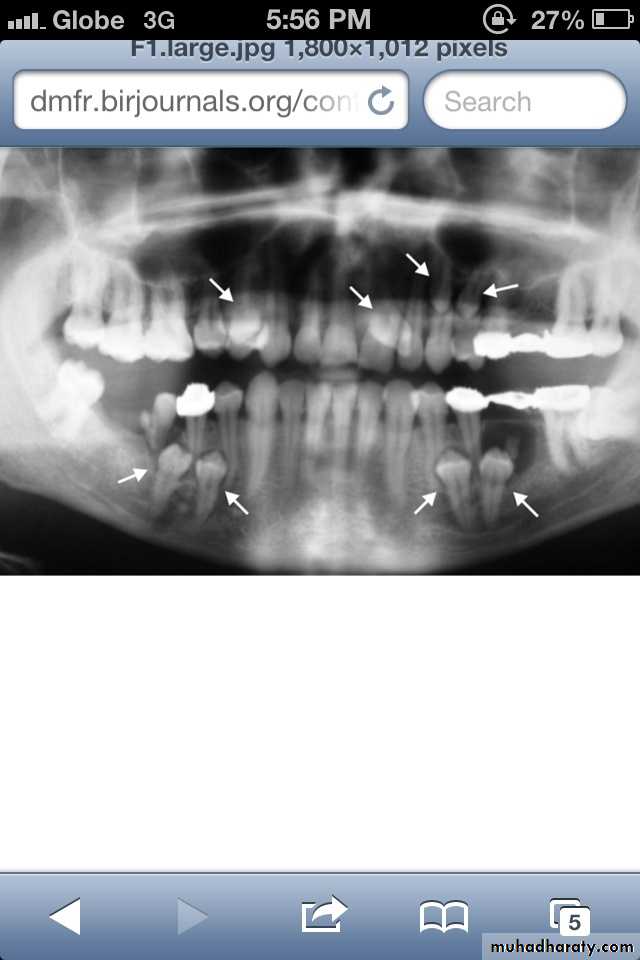

Paramolar blocking the eruption of 3rd molar.

MesiodensDistomolars(4th molar)

Mesiodens

Distodens or distomolarParamolar

Supplemental